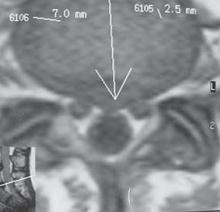

На МРТ № 11 наблюдается парамедианная грыжа межпозвонкового диска, которая как бы обхватывает с двух сторон спинной мозг На МРТ № 12 наблюдается медианная (срединная) грыжа межпозвонкового диска, которая часто протекает безсимптомно и может достигать больших размеров МРТ № 13 ![]() МРТ № 14